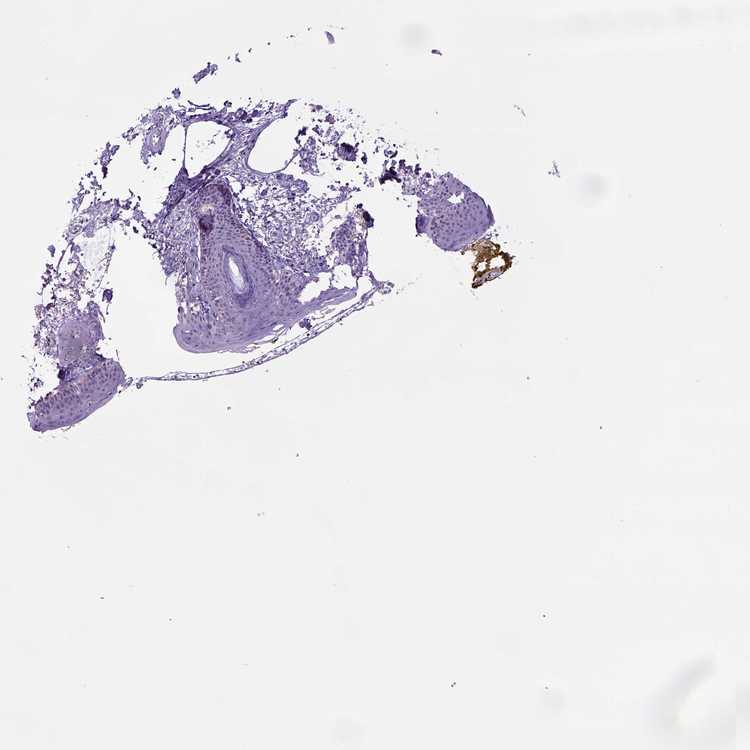

SKIN 1 - Antibody stainingi

Antibody staining in the annotated cell types in the current human tissue is reported as not detected, low, medium, or high, based on conventional immunohistochemistry profiling in selected tissues. This score is based on the combination of the staining intensity and fraction of stained cells.

Each image is clickable and will lead to virtual microscopy that enables deeper exploration of all samples and also displays staining intensity scores, fraction scores and subcellular localization as well as patient and tissue information for each sample.

Antibody HPA050786

Langerhans Not detected

Fibroblasts Not detected

Keratinocytes Not detected

Melanocytes Not detected